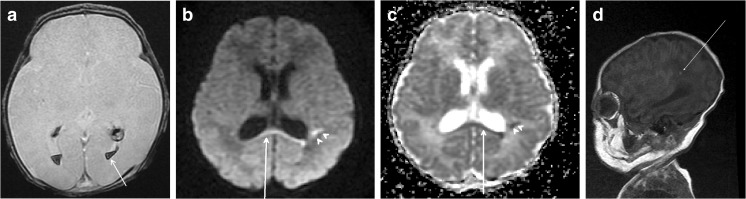

Fig. 3.

A 13-day-old female neonate was transferred to our hospital because of a seizure. She was delivered by an elective cesarean section and had a PDA and ASD. Apgar scores at 1 and 5 min were 8 and 10, respectively. MRI obtained 16 days postnatally showed a bilateral intraventricular hemorrhage on axial GE imaging and b, c diffusion restriction of the corpus callosum (arrow) and high-signal foci in both frontoparietal periventricular white matters (arrowheads) on axial DW and ADC map. d Several high-signal foci were observed in the left periventricular white matter on T1 sagittal scan (arrow). Bayley scale evaluation at 8 months showed normal development

SDH was the most common type of hemorrhage (40/42, 95.2%). Seven SAH, one EDH (Fig. 2), three GMH (Fig. 3), and nine intraparenchymal hemorrhages were identified. A total of 16 infants had two or more types of hemorrhage. SDH was commonly located along the tentorium (n = 38), over the cerebellar hemispheres (n = 39), along the interhemispheric fissure (n = 10), over the occipital lobes (n = 13), and parietooccipital lobes (n = 11). The frontal (n = 4), parietal (n = 3), and cerebellar (n = 2) lobes were most commonly involved in patients with intraparenchymal hemorrhage. A single lobe was involved in eight of nine infants with intraparenchymal hemorrhage. There was no significant correlation between the clinical outcome and site of hemorrhage. SDH was resolved or decreased in follow-up patients (9/42, 21.4%).